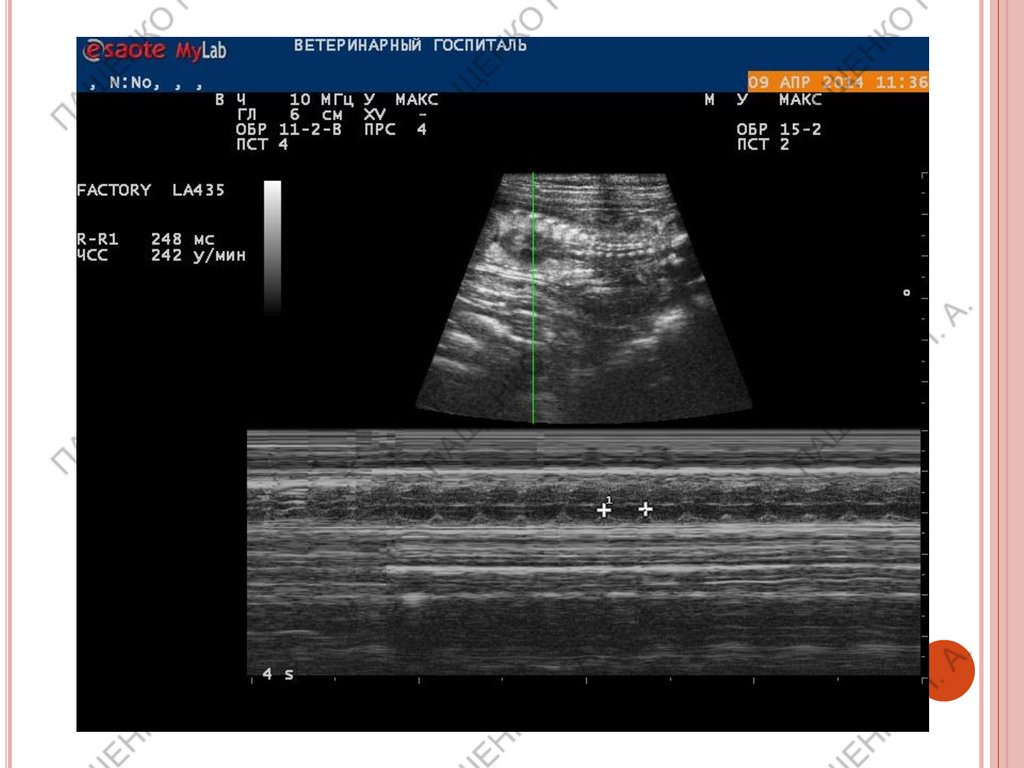

патологических структур,

Подсчет ЧСС плодов обязателен на поздних

сроках беременности.

ВАЖНО!

При ЧСС выше 180 уд/мин– норма

ЧСС ниже 180 уд/мин– нужен мониторинг.

ЧСС 160-140 уд/мин – кесарево сечение в

течении 2х часов

ЧСС менее 140 уд/мин – необходимо

экстренное кесарево!